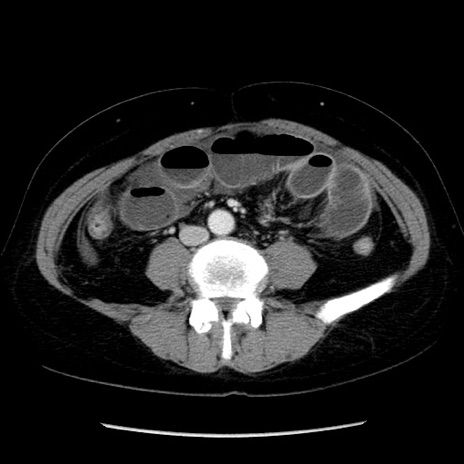

冠状断像

矢状断像